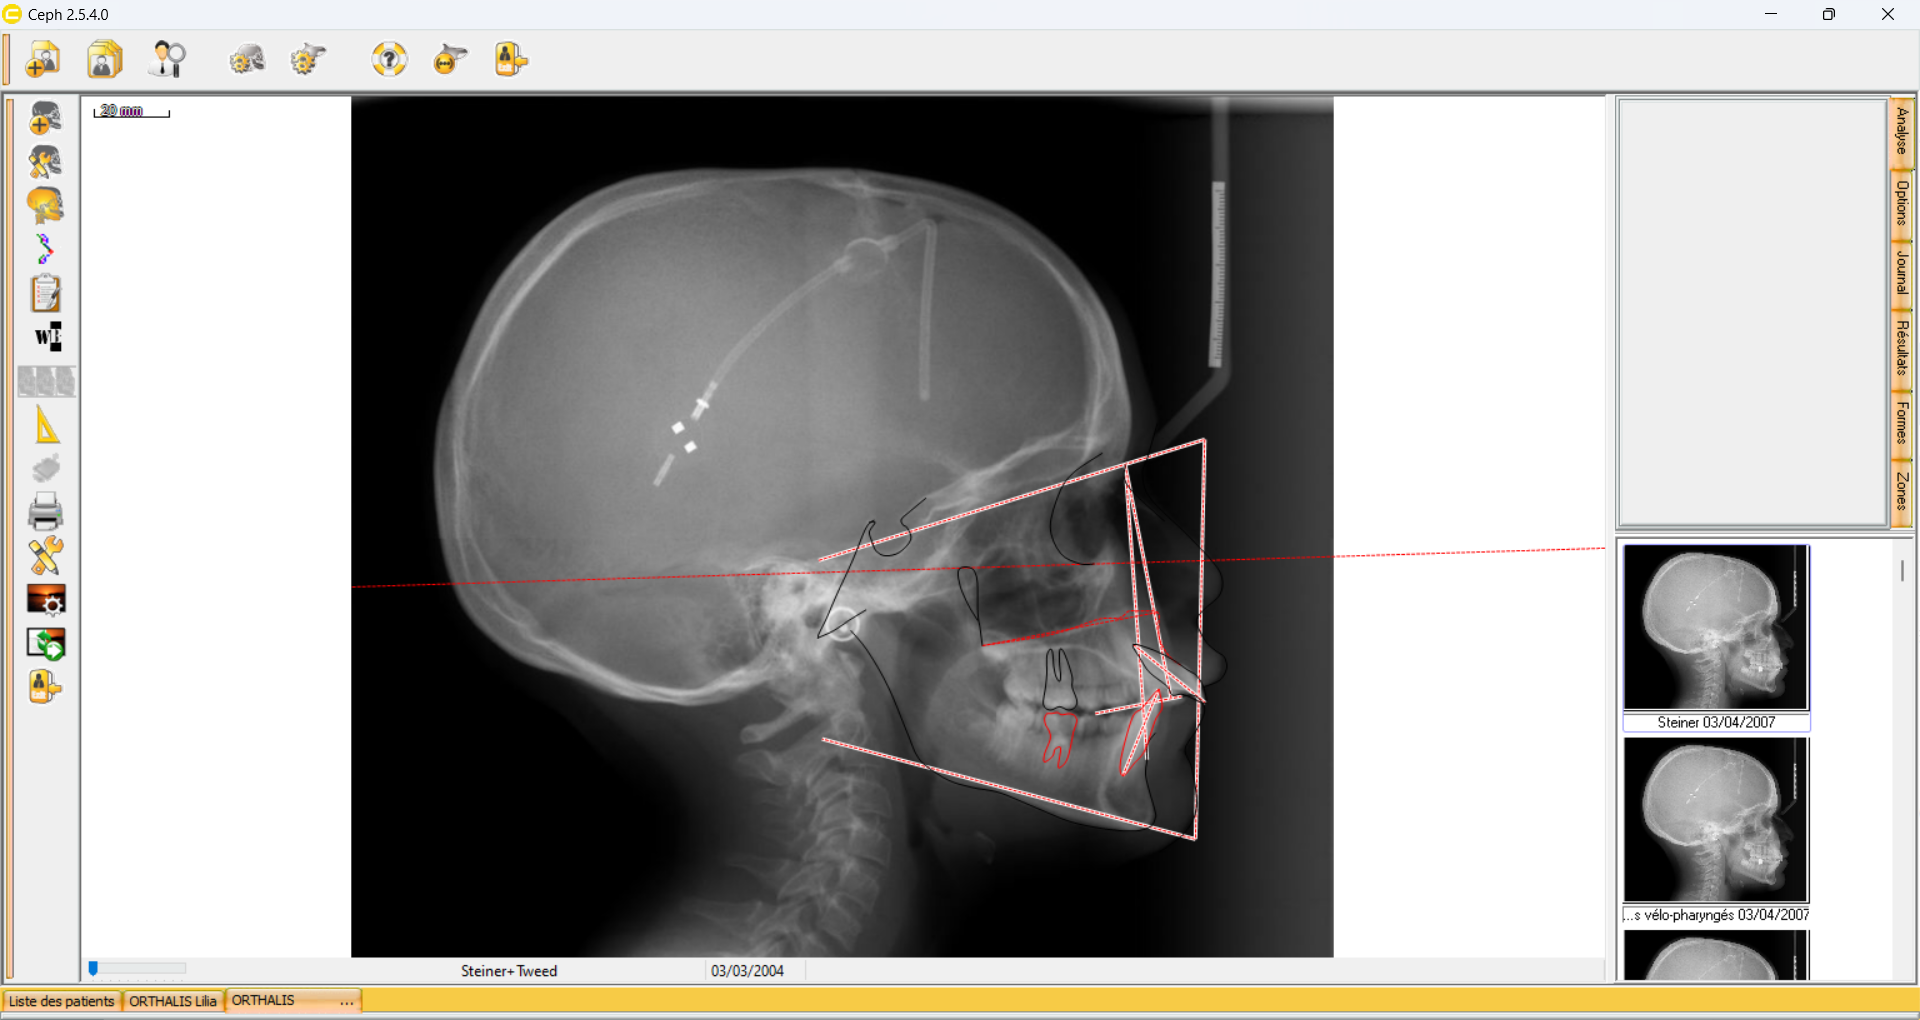

Le logiciel nous demandes maintenant de sélectionner les points à superposer pour établir le plan de superposition.

Dans cet exemple nous choisissons Sur SNa en Na. Suivant.

Un récapitulatif apparait.

Choisir Terminé.

Voici la superposition: